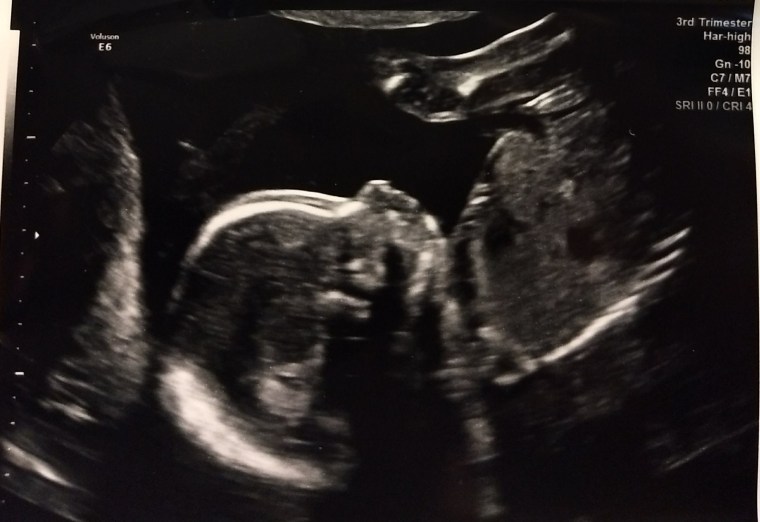

Getting pregnant with baby # 2: For some reason I always worried about having trouble conceiving and I imagined it taking a while. I am so unbelievably blessed and grateful that I got pregnant (and stayed pregnant) so easily not only with Jackson, but with our second baby as well. In both cases, we conceived on the first try, which I know is very lucky and something I shouldn’t take for granted. I know many people who have struggled with either infertility or pregnancy loss or both, and I count my lucky stars that we have been so fortunate in this area.